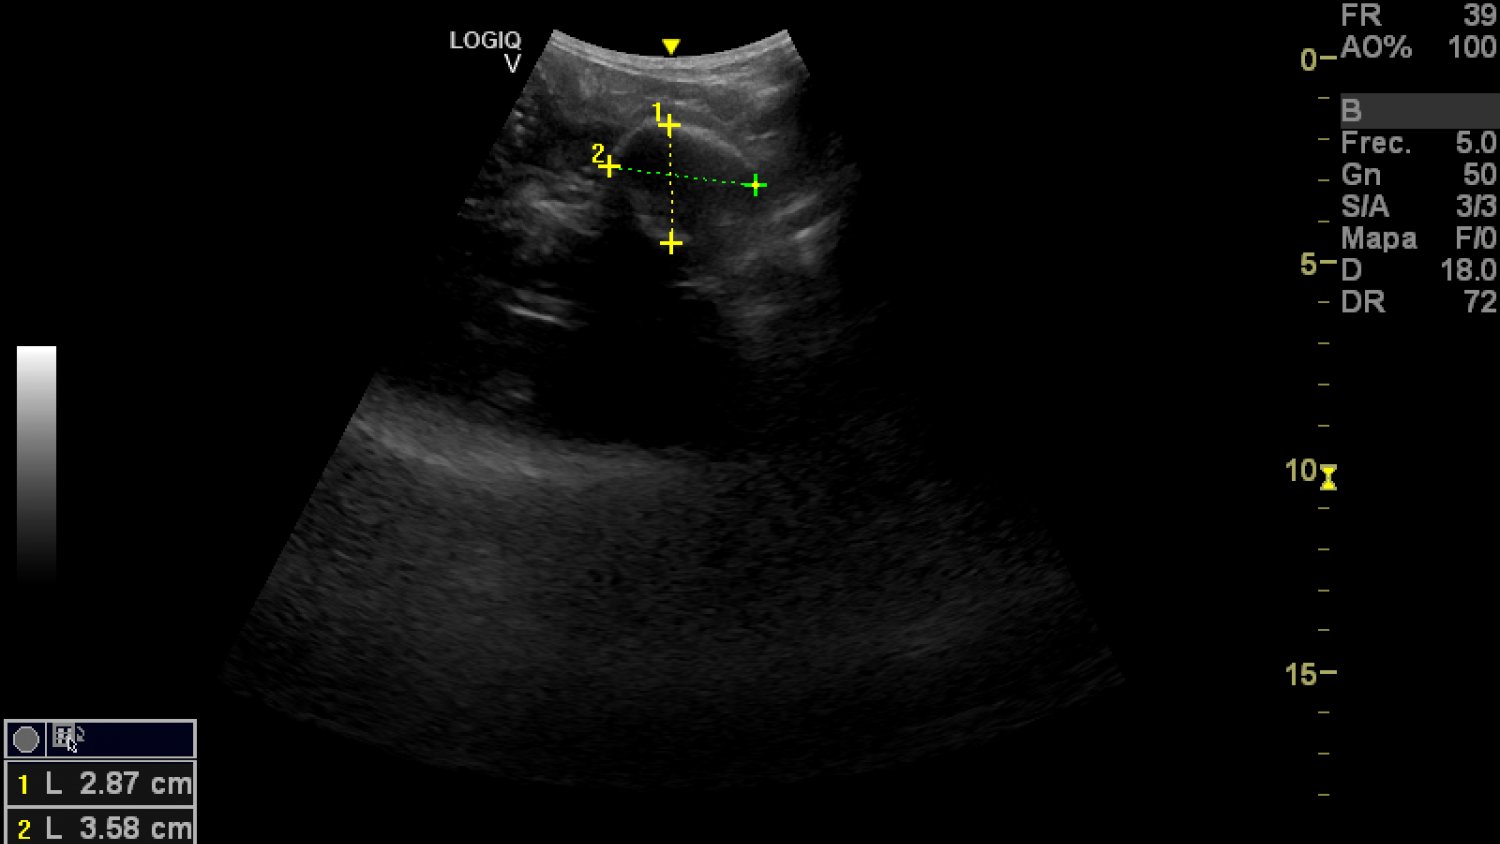

Medición de cráneo del perezoso./ BIOPARC Fuengirola

El seguimiento de la gestación se está realizando dentro de los protocolos habituales de cuidado y bienestar del animal, integrando revisiones veterinarias voluntarias y sin ningún tipo de riesgo. Entre ellas se incluyen ecografías realizadas como parte de su rutina diaria, posibles gracias a un avanzado programa de entrenamiento veterinario desarrollado por los equipos de Zoología y Veterinaria de BIOPARC Fuengirola.

Gracias a un proceso progresivo de desensibilización y familiarización, los cuidadores han logrado que Reina acepte de forma natural la presencia del equipo veterinario y el contacto necesario para la exploración abdominal. Para ello, se han simulado previamente las condiciones reales del procedimiento mediante el uso de instrumentos similares a la sonda ecográfica, presiones controladas y la aplicación de geles, siempre sin contacto protegido y bajo estrictas medidas de seguridad. Este trabajo permite monitorizar de forma regular el desarrollo fetal, la frecuencia cardiaca y el estado general de la madre sin alterar su comportamiento.

El embarazo comenzó a sospecharse tras el registro detallado de las cópulas y la posterior observación de una leve distensión abdominal en los últimos meses, apenas perceptible para ojos no expertos. Esta discreción no es casual: se trata de una adaptación evolutiva que permite a los perezosos pasar desapercibidos frente a depredadores como grandes rapaces, felinos o serpientes constrictoras. Los controles veterinarios confirman que el feto se desarrolla con normalidad y a buen ritmo, mientras que Reina mantiene una conducta, alimentación y rutina completamente estables.

El periodo de gestación de esta especie es especialmente largo, con una media estimada de entre 330 y 350 días, aunque existen importantes variaciones descritas en la literatura científica. En estos momentos, los especialistas sitúan a Reina en el último tercio del embarazo, una fase clave que se afronta con un seguimiento continuo y adaptado a sus necesidades.